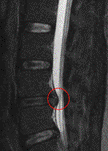

左の画像は、椎間板が神経を圧迫している(ヘルニア)のMRI画像です。 今までの考え方だと…

確かに痛そうです。

下の円グラフは、健常者だけのMRI画像の結果です。腰が痛くない健常者の中でも、椎間板の異常がかなり高い割合で見つかるのです。

MRIやレントゲンに写る椎間板の異常も痛みの原因とは考えにくいのです。 |

(Jenson MC. et al:N Engl J Med, 1994より)